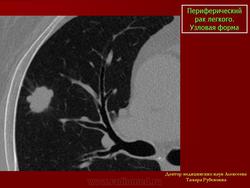

Периферический рак легкого. Узловая форма.

Для всех периферических раков наиболее характерна узловая форма роста опухоли. Независимо от гистологического строения периферического рака легкого располагаются опухоли наиболее часто во втором сегменте верхней доли и локализуются в различных отделах: прикорневом, ядерном и плащевом.

Если рассматривать форму опухолевого узла в зависимости от гистологического строения то можно отметить, для периферического ПКРЛ наиболее характерной является округлая.

Рентгенологические проявления узловой формы периферической аденокарциномы зависят от размеров опухоли. Если размеры опухолевых узлов не превышают 1,5см. полигональная форма, до 3,0 см округлая, когда размеры опухоли 5,0 см и больше форма становится неправильной.

Изучению рентгеносемиотических признаков периферического рака легкого и особенно его малых форм посвящено большое количество исследований. Классическими рентгенологическими признаками рака легкого считается сочетание бугристой поверхности и лучистости по контуру.